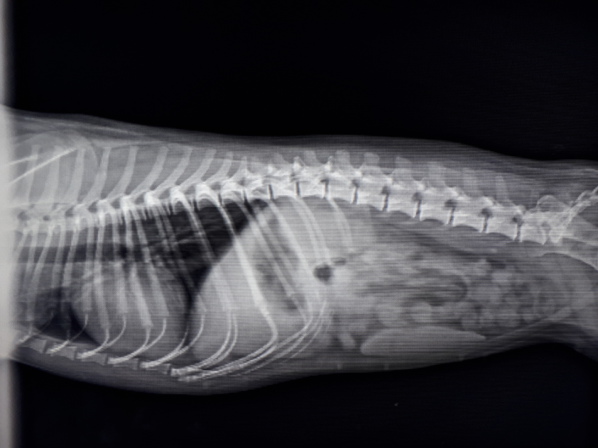

Wir bieten in unserer Praxis digitales Röntgen an. Die Röntgenstrahlen werden hierbei elektronisch auf einer Platte gespeichert. Die so gewonnenen Bilder sind sofort auf einem großen Bildschirm einsehbar. Digitales Röntgen macht eine schnelle und qualitativ hochwertige Auflösung der Bilder und damit einhergehender Diagnostik möglich.